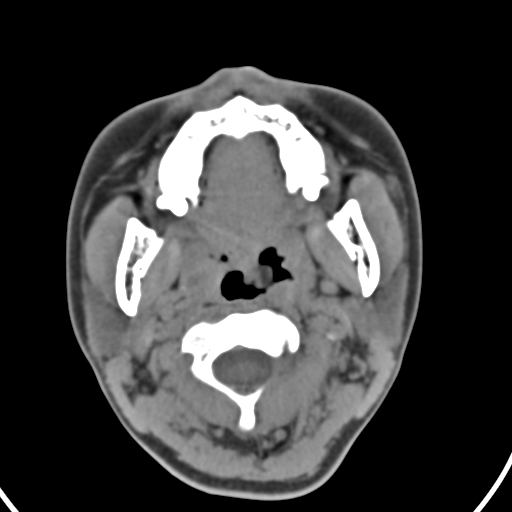

以下是引用zjzjr在2008-12-5 11:46:00的发言:[br]脂肪密度,壁有钙化.考虑口咽部皮样囊肿可能性大.双侧上颌窦炎,双侧下鼻甲粘膜肥厚.增殖腺肥大,扁桃体亦增大,考虑炎性.

以下是引用随光逐影在2008-12-5 18:27:00的发言:[br]1)考虑左侧茎突过长综合征并茎突舌骨韧带囊肿形成突入咽部;左侧咽部慢性炎症。2)鼻咽腺样体肥大。3)双侧扁桃体肿大。4)双侧上颌窦炎。5)双侧下鼻甲粘膜肥厚。